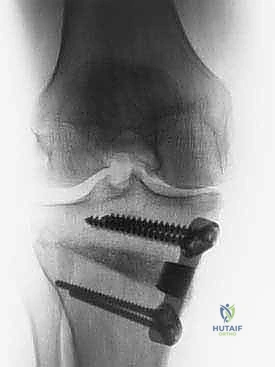

* الشق المفتوح (Opening Wedge): يتم فتح العظم من الداخل وإضافة طعم عظمي (صناعي أو طبيعي) لملء الفراغ وتعديل الزاوية. وهي الطريقة الأكثر شيوعاً حالياً.

* الشق المغلق (Closing Wedge): يتم إزالة إسفين (مثلث) صغير من العظم من الجهة الخارجية وإغلاق الفراغ.

4. تعديل المحور:

يتم فتح العظم تدريجياً وببطء شديد حتى الوصول إلى الزاوية التي تم حسابها في التخطيط الرقمي قبل الجراحة.